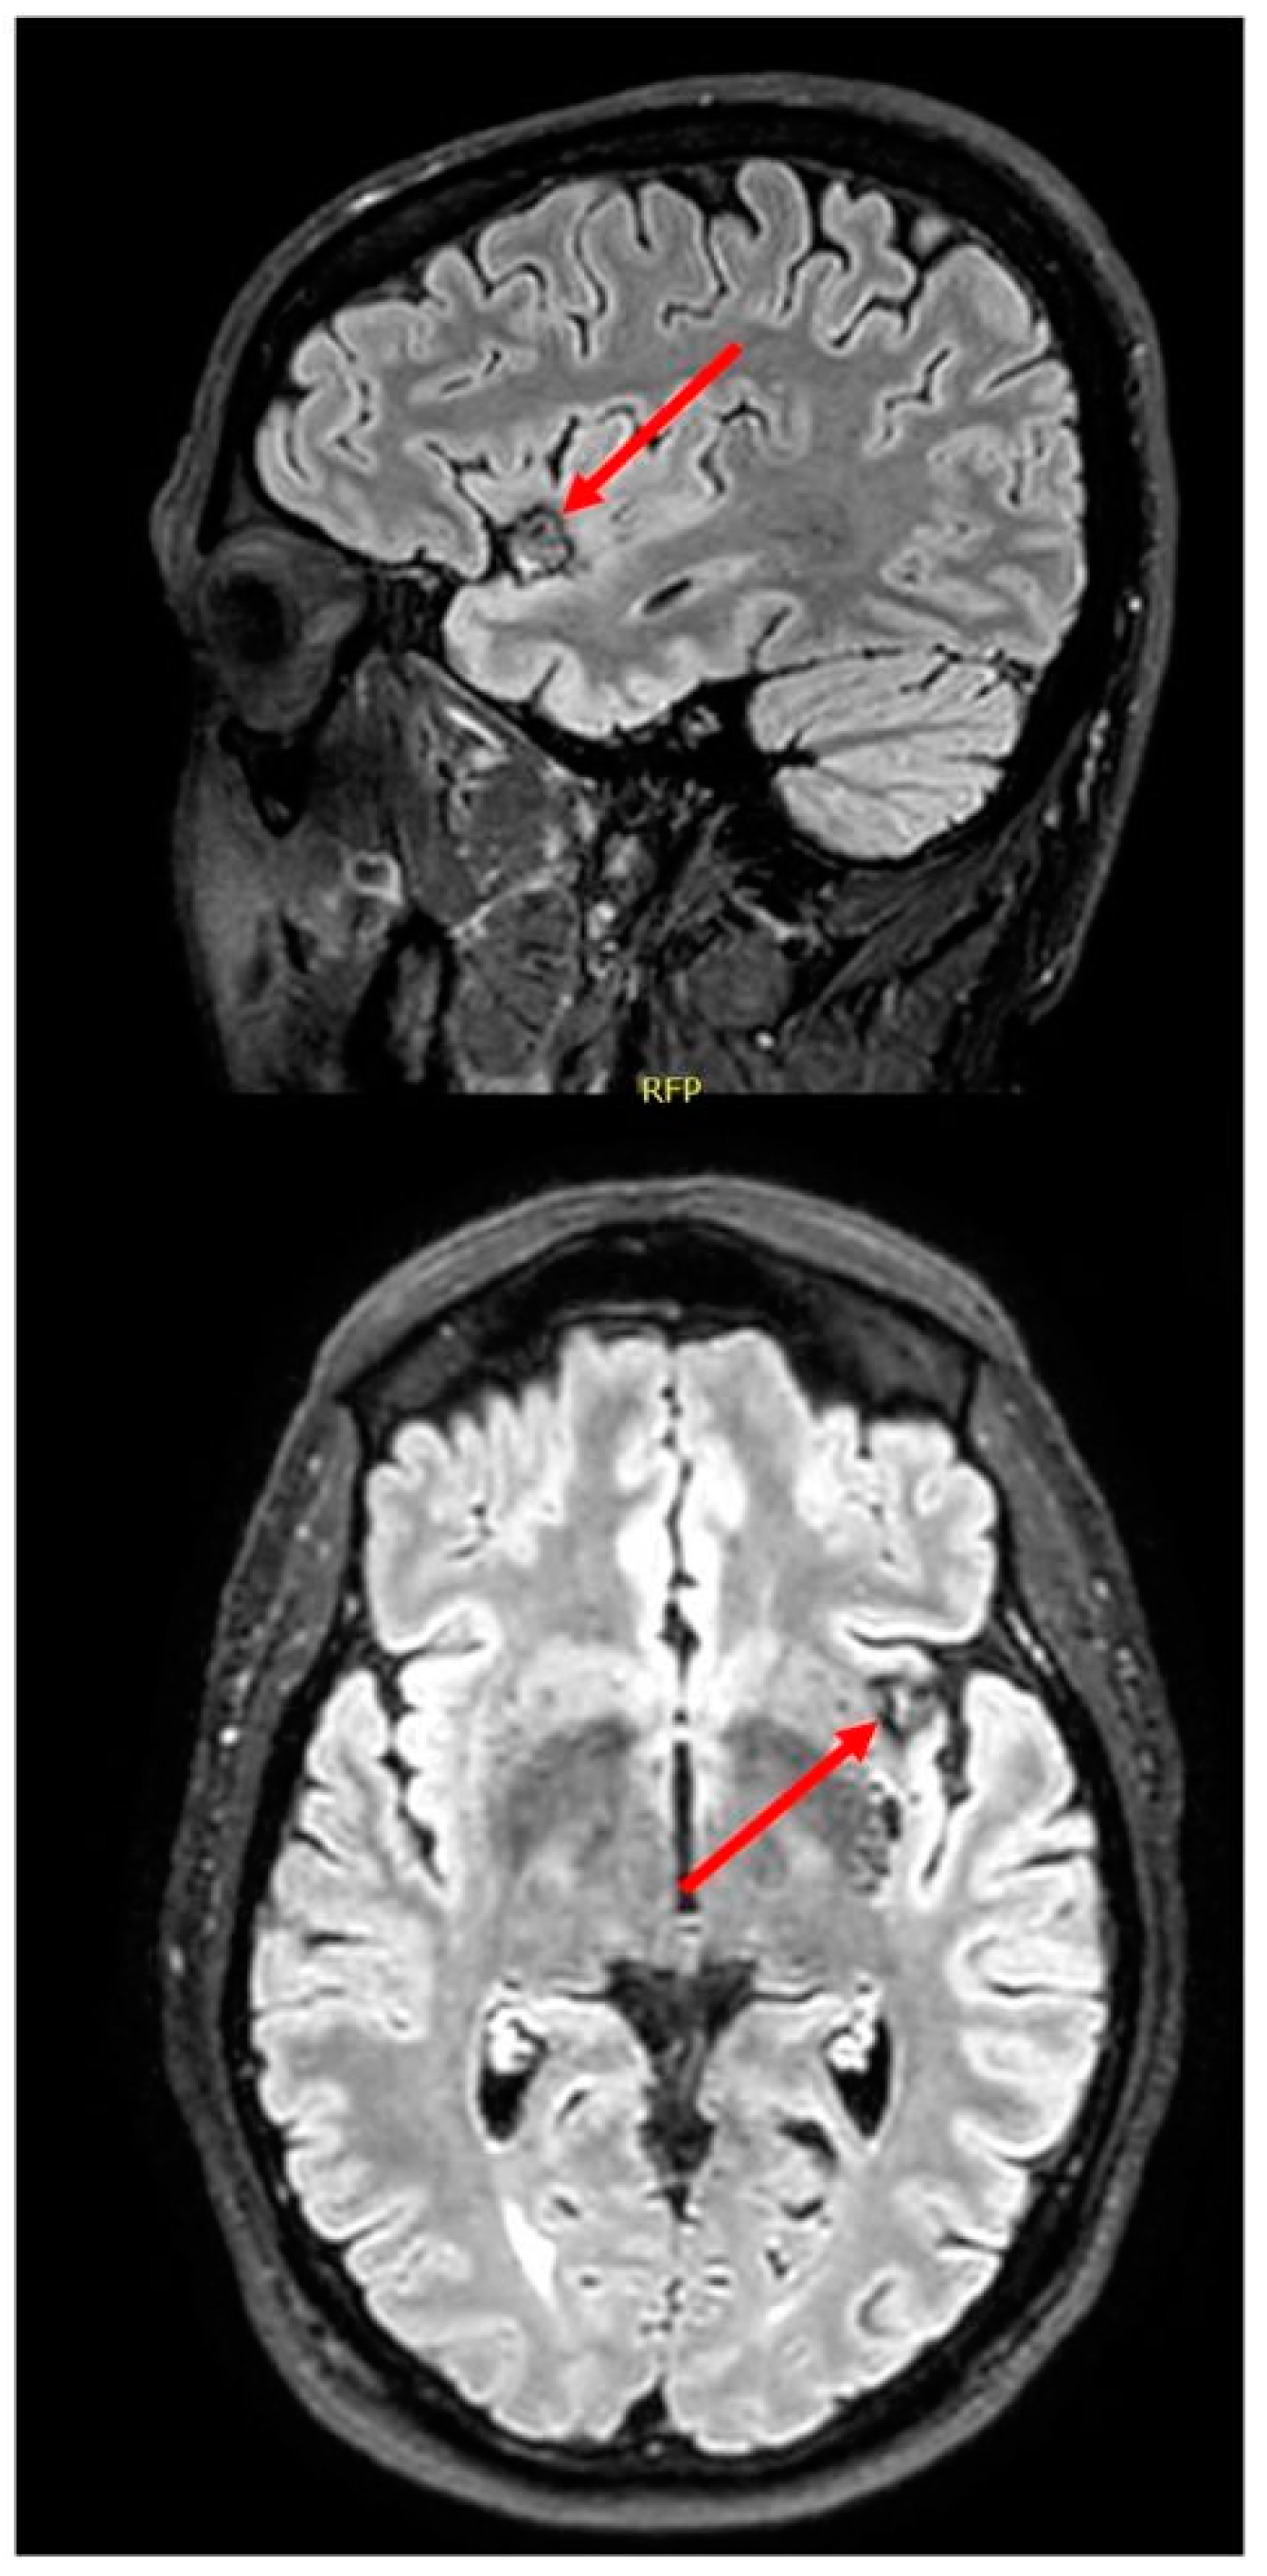

3. Case Study

3.2. Results